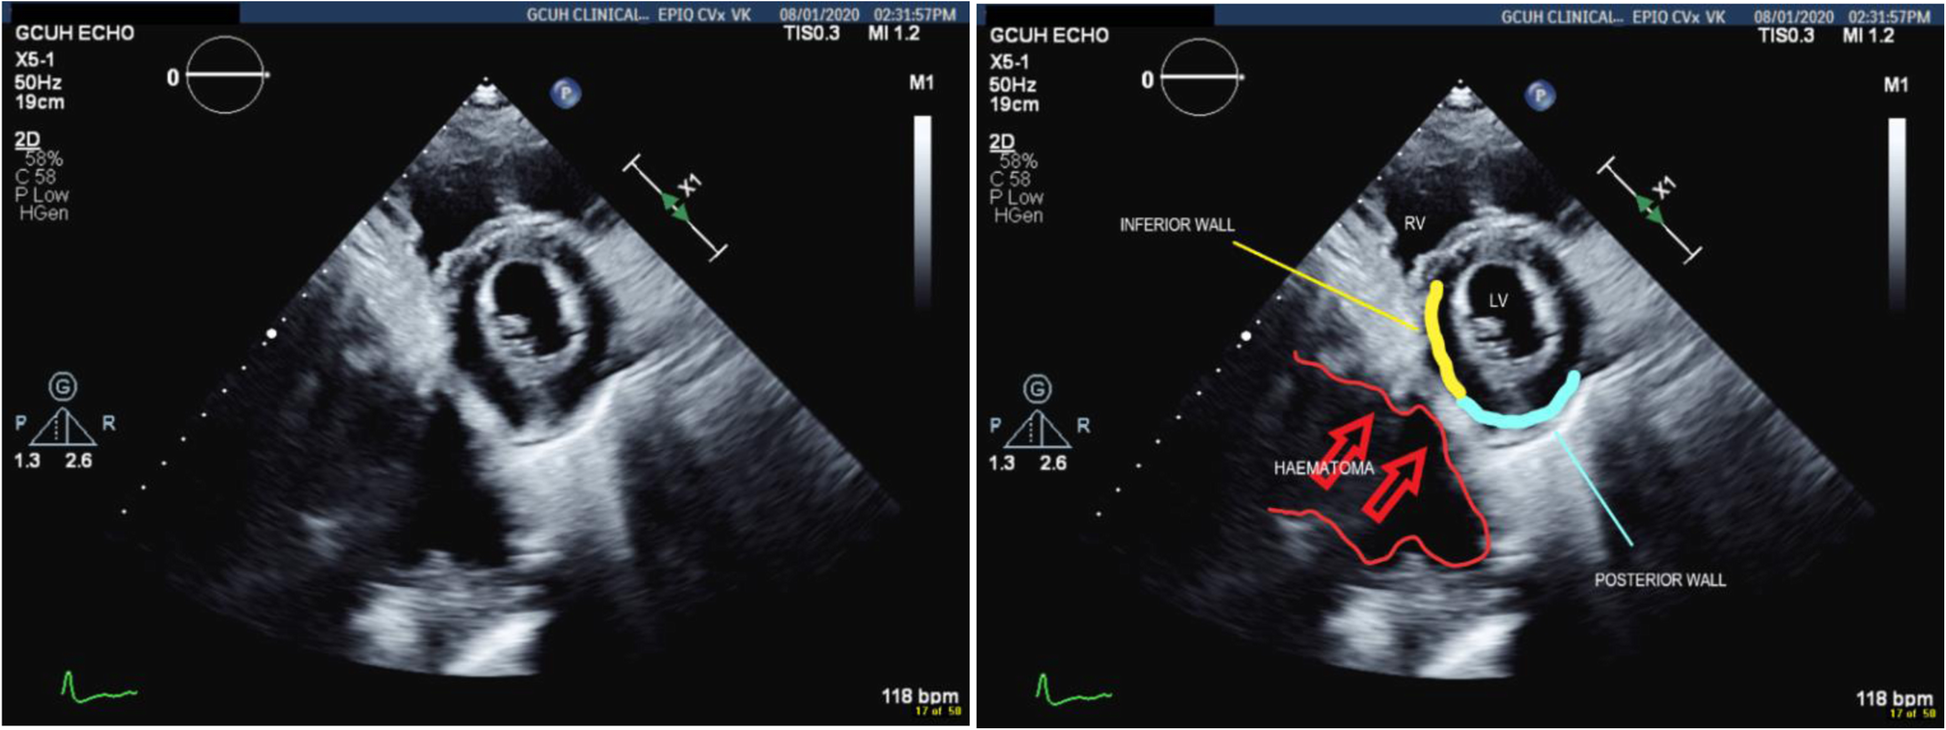

TTE confirmed retrocardiac compression as a result of the expanding retroperitoneal haematoma (Figs. 6 and 7).

Fig. 6

Parasternal long axis view showing the haematoma compressing the posterior wall of the LV

Bild vergrößern

Fig. 7

Short axis view showing the haematoma compressing both posterior and inferior walls of the LV